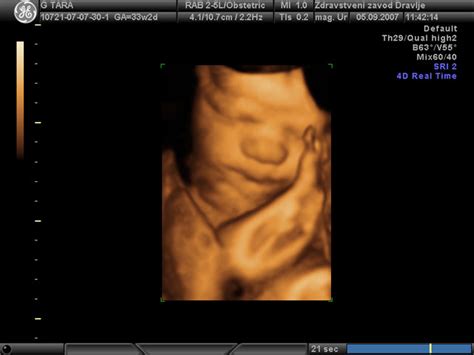

Otrokove noge so tesno privite k telesu, saj mu v maternici že primanjkuje prostora, zato se nahaja v tako imenovanem fetalnem položaju, z nogami privitimi k prsnemu košu. Občasno sesa svoj nožni palec, s čimer uri sesalni refleks. Njegove roke so prekrižane čez trebušček, med njima pa je popkovina, ki jo otrok vsake toliko časa močno potegne. Na tej stopnji je otrok skoraj popolnoma razvit in je že viden kot majhen novorojenček. Še vedno pa pridobiva podkožno maščobo, zaradi katere postaja nekoliko bolj zalit in izginjajo še preostale kožne gube. Otrokove kože postaja gladka, mehka in ni več tako nagubana, zahvaljujoč podkožni maščobi. V tem tednu ima vaš dojenček morda že polno las, ali pa le puhek. Njegovi nohti na rokah in nogah so že skoraj popolnoma razviti.

V 32. tednu nosečnosti bo otrok meril približno 42 centimetrov od glave do pet in tehtal okoli 2150 gramov. Predstavljajte si, otrok bo v zadnjih 8 tednih do poroda pridobil od 1,5 do 2 kilograma! Vaš dojenček najbrž tehta že več kot kilogram in pol, velik pa je že okrog 42 centimetrov. V tem tednu ima vaš dojenček morda že polno las, ali pa le puhek. Njegovi nohti na rokah in nogah so že skoraj popolnoma razviti. Plod ima zdaj že prave nohte in lase, koža pa postaja gladka, mehka in ni več tako nagubana, zahvaljujoč podkožni maščobi. Otrok še naprej trenira in razvija tudi svoja čutila, ki mu bodo po rojstvu omogočila zaznavanje in odzivanje na svet okoli sebe.

Otrokovo telo je skoraj v celoti oblikovano in razvoj organov je končan, le par stvari še manjka, da bodo svojo funkcijo opravljali optimalno. Ker otroku v maternici že primanjkuje prostora, je vedno bolj tesno zvit v tako imenovanem fetalnem položaju, z nogami privitimi k prsnemu košu. Otrokove noge so tesno privite k telesu, otrok pa občasno sesa svoj nožni palec in tako še naprej uri sesalni refleks. Njegove roke so prekrižane čez trebušček, med njima pa je popkovina, ki jo otrok občasno močno potegne. Na tej stopnji je otrok skoraj popolnoma razvit in je že videti kot majhen novorojenček. Še vedno pa pridobiva podkožno maščobo, zaradi katere postaja nekoliko bolj zalit in izginjajo še preostale kožne gube.